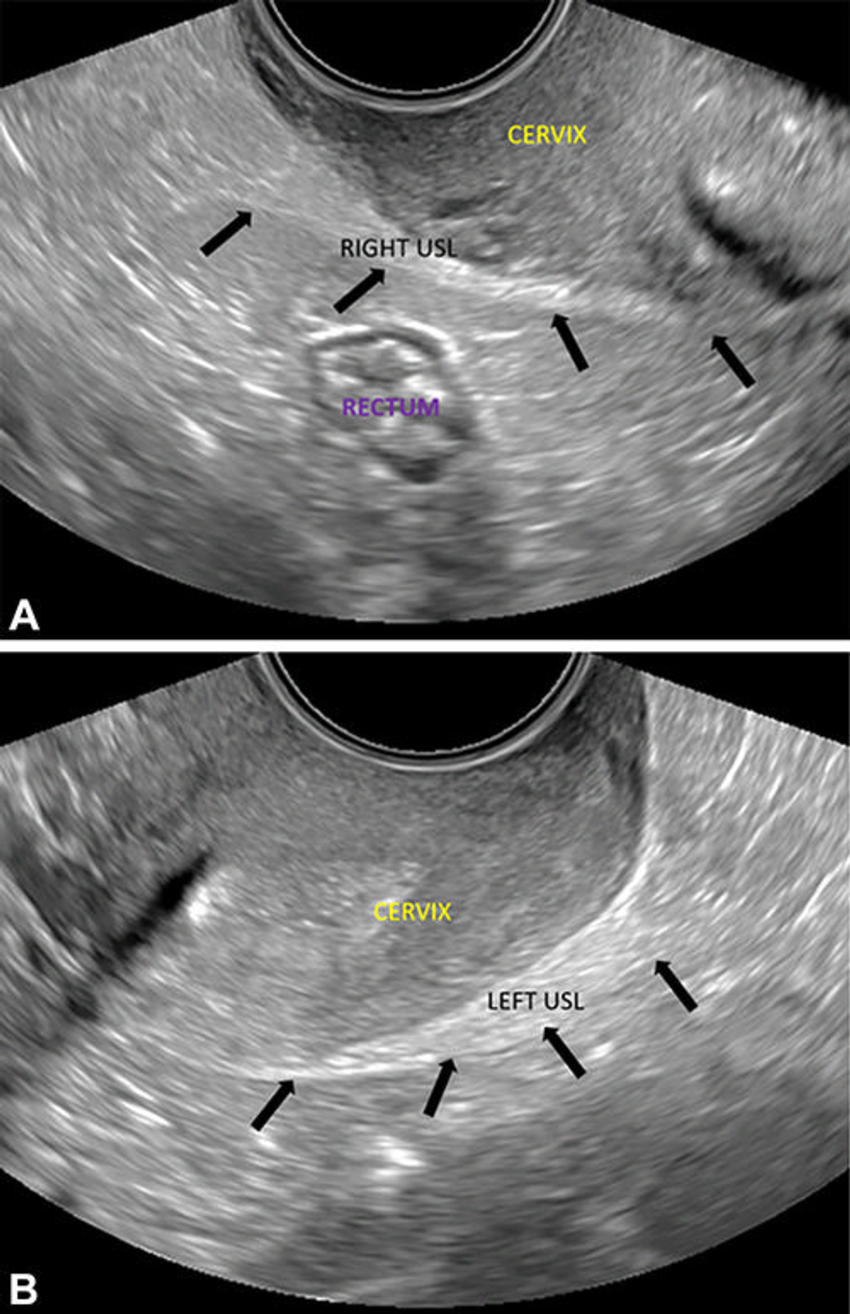

Figure 1. Transvaginal US images show the posterior compartment in a 25-year-old patient with dysmenorrhea, on the retrocervical field of view (area of interest outlined in yellow), 4–5-cm deep to the cervix. Longitudinal (A) and transverse (B) views. The transducer is in the anterior fornix. Longitudinal and transverse sweeps were acquired to include these areas.

Figure 3. Transvaginal US in normal right and left uterosacral ligaments (USL) in a 32-year-old patient with chronic pelvic pain and echogenic bands insert near the posterior cervicouterine junction (arrows, A and B). Transverse oblique images show the (A) right and (B) left anterolateral fornices.